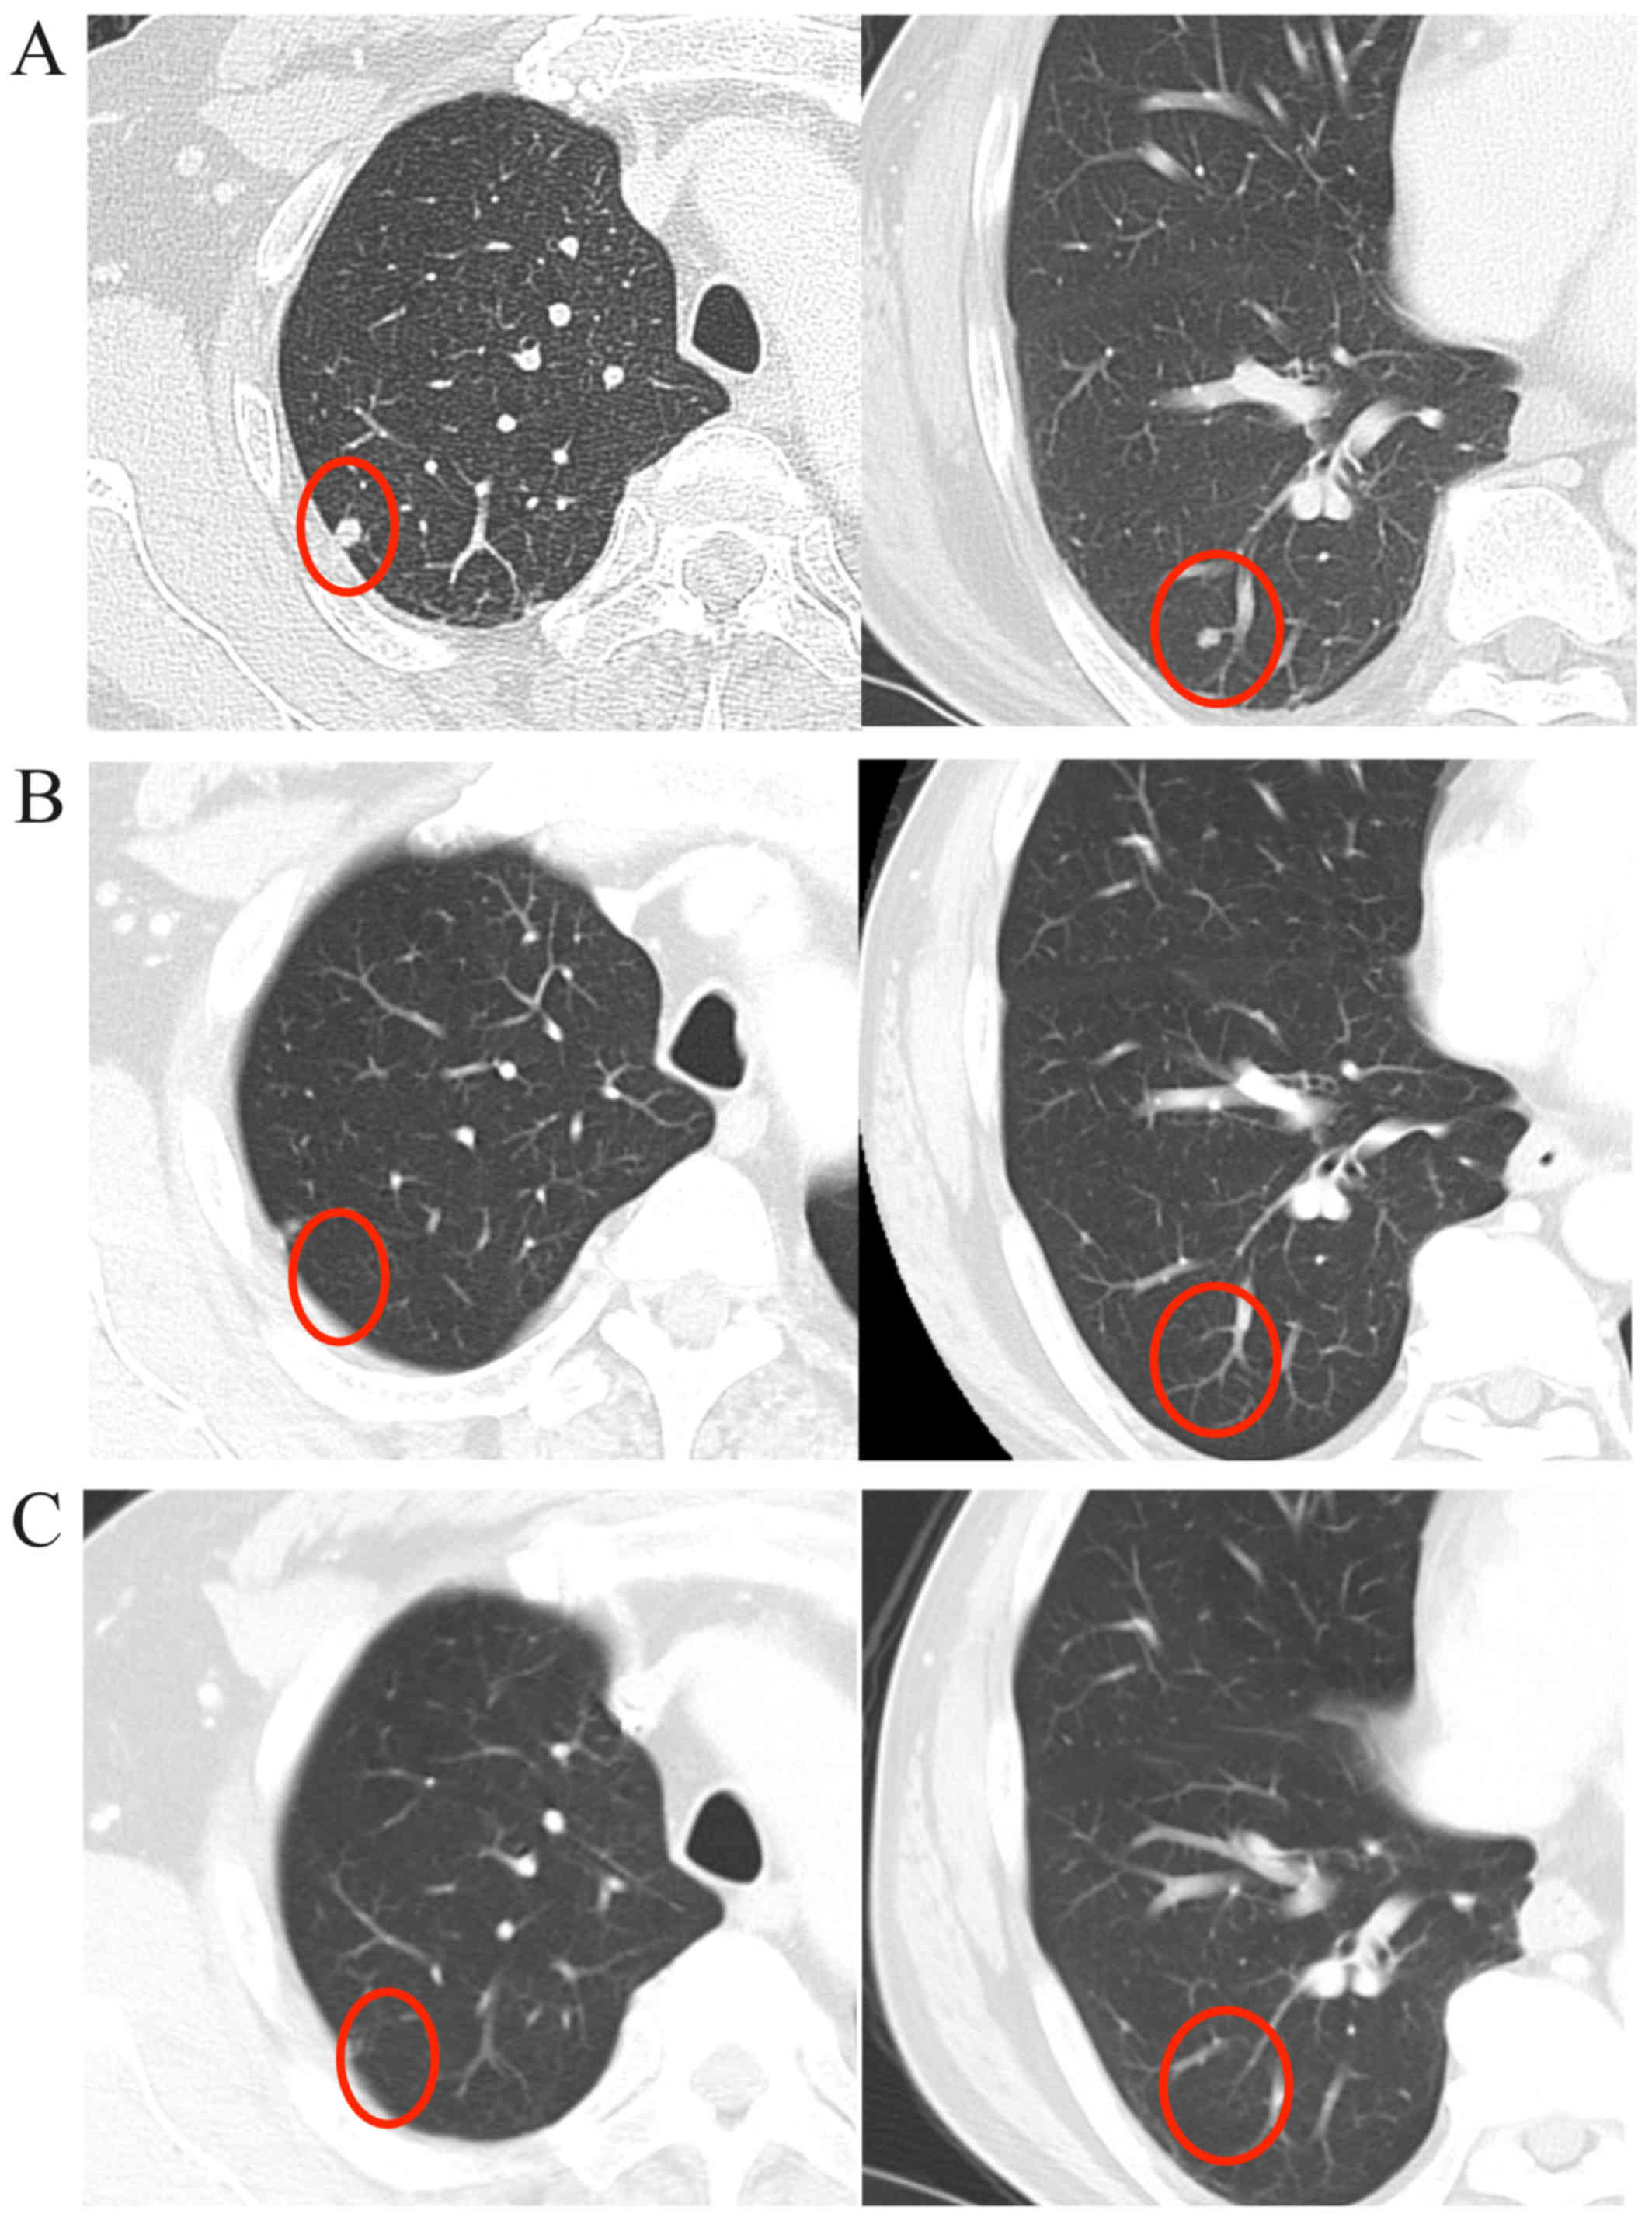

Salivary duct carcinoma is a highly aggressive disease with a poor prognosis. Surgical resection is currently the only curative treatment, as there is no effective systemic therapy for this malignancy. Recently, trastuzumab has been shown to exhibit therapeutic efficacy in the treatment of salivary duct carcinoma; similarly, molecularly targeted agents, such as cetuximab, are expected to be useful for salivary duct carcinoma treatment. We herein describe the case of a 56-year-old man diagnosed with salivary duct carcinoma in the left submandibular region, with ipsilateral multiple metastases to the neck lymph nodes. Radical resection of the tumor and submandibular gland with neck dissection were performed. One month after radical surgery, computed tomography (CT) scans indicated metastasis in the lower lobe of the left lung. CT‑guided transthoracic fine‑needle aspiration biopsy revealed a single metastasis and lung metastasectomy was immediately performed. The tumor cells of the primary lesion and those of the lung metastasis were immunohistochemically positive for epidermal growth factor receptor. One month later, multiple right lung metastases appeared, and the patient was treated with cisplatin/5‑fluorouracil (5‑FU) chemotherapy plus cetuximab, achieving a complete radiographic response. However, multiple lung metastases developed during adjuvant weekly cetuximab monotherapy. Subsequently, treatment with S‑1 and weekly cetuximab was initiated, and the multiple lung metastases have been maintained as stable disease for 5 months. To the best of our knowledge, this is the first report of cetuximab use for the treatment of salivary duct carcinoma. Although cisplatin/5‑FU chemotherapy plus cetuximab was efficacious in treating the lung metastasis, cetuximab monotherapy was insufficient for controlling tumor growth.